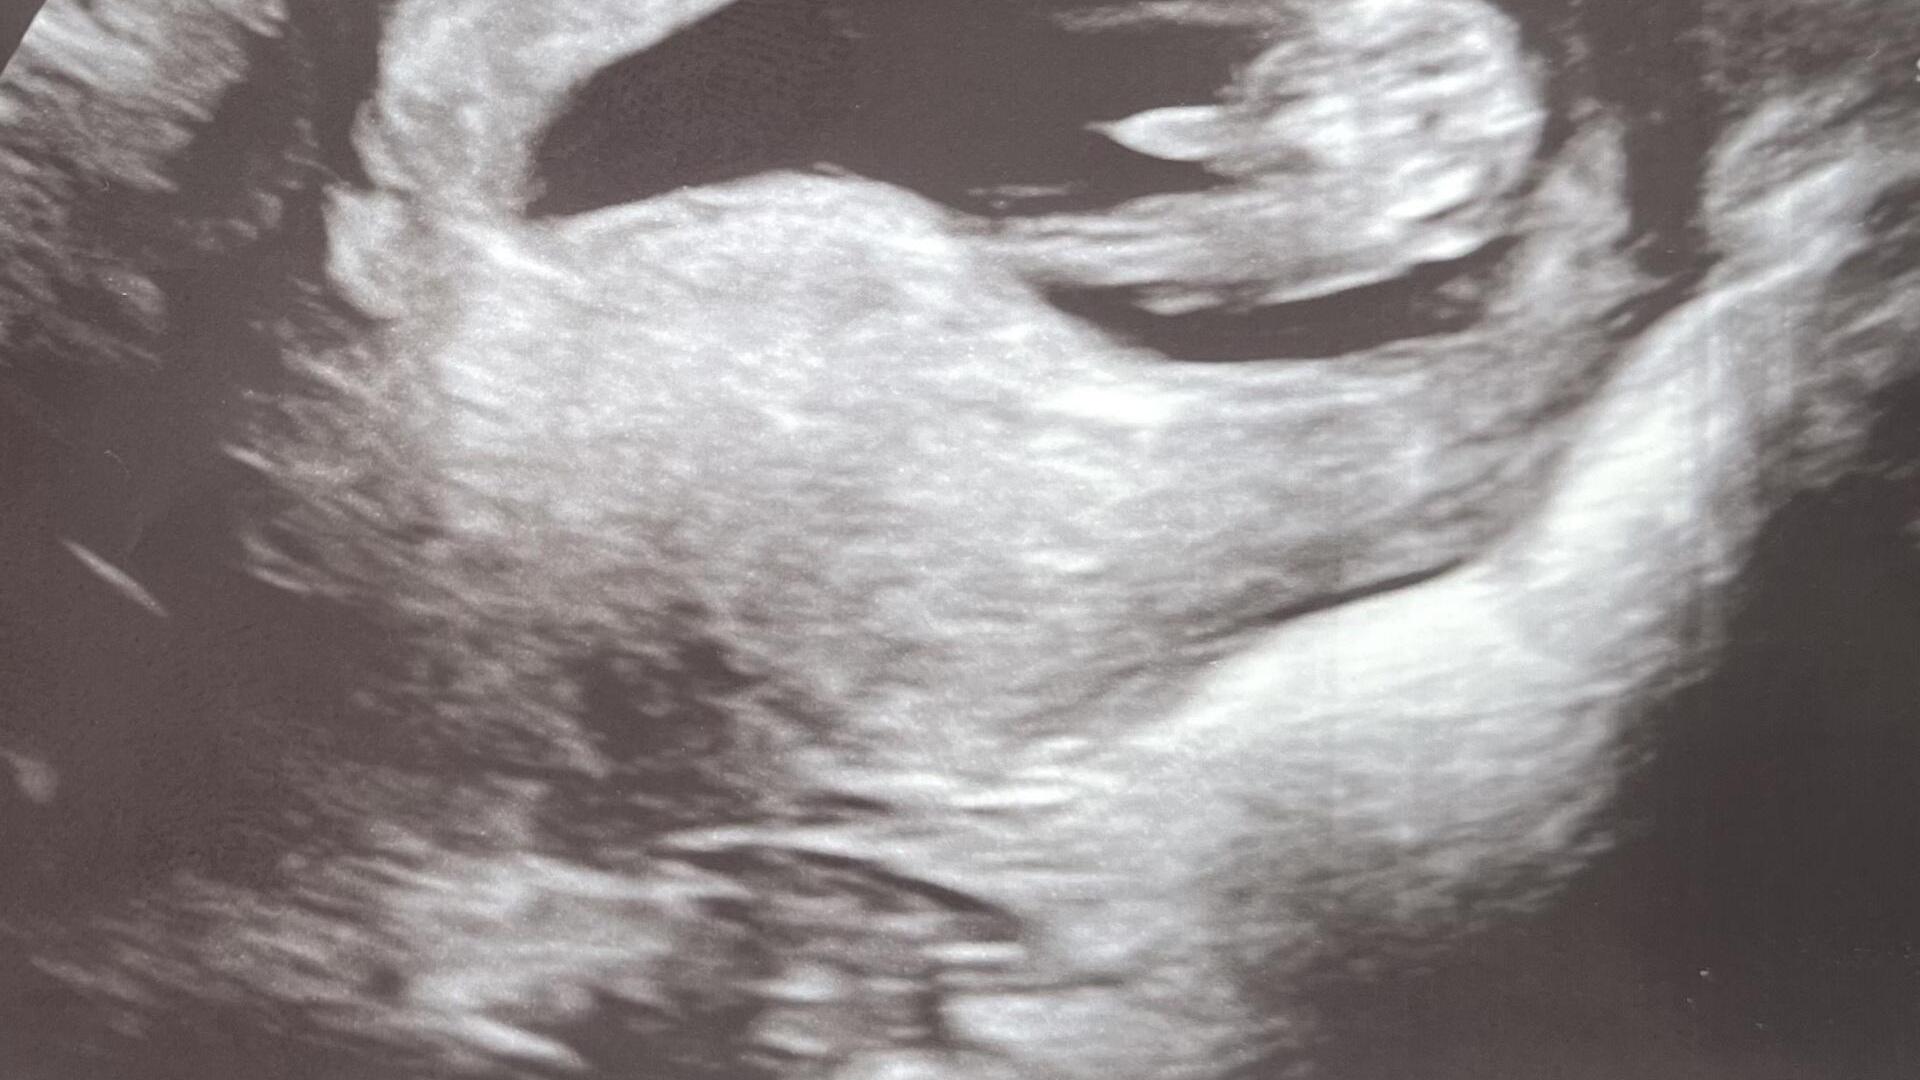

¨Foto: Pupeční šňůra nebo bimbas?

Pohlaví může jít vidět na prvním screeningu, nám řekli ve 13tt kluk, s jistotou, pak uz jen potvrzovali a kluka mame, priste se zeptej :kytka: